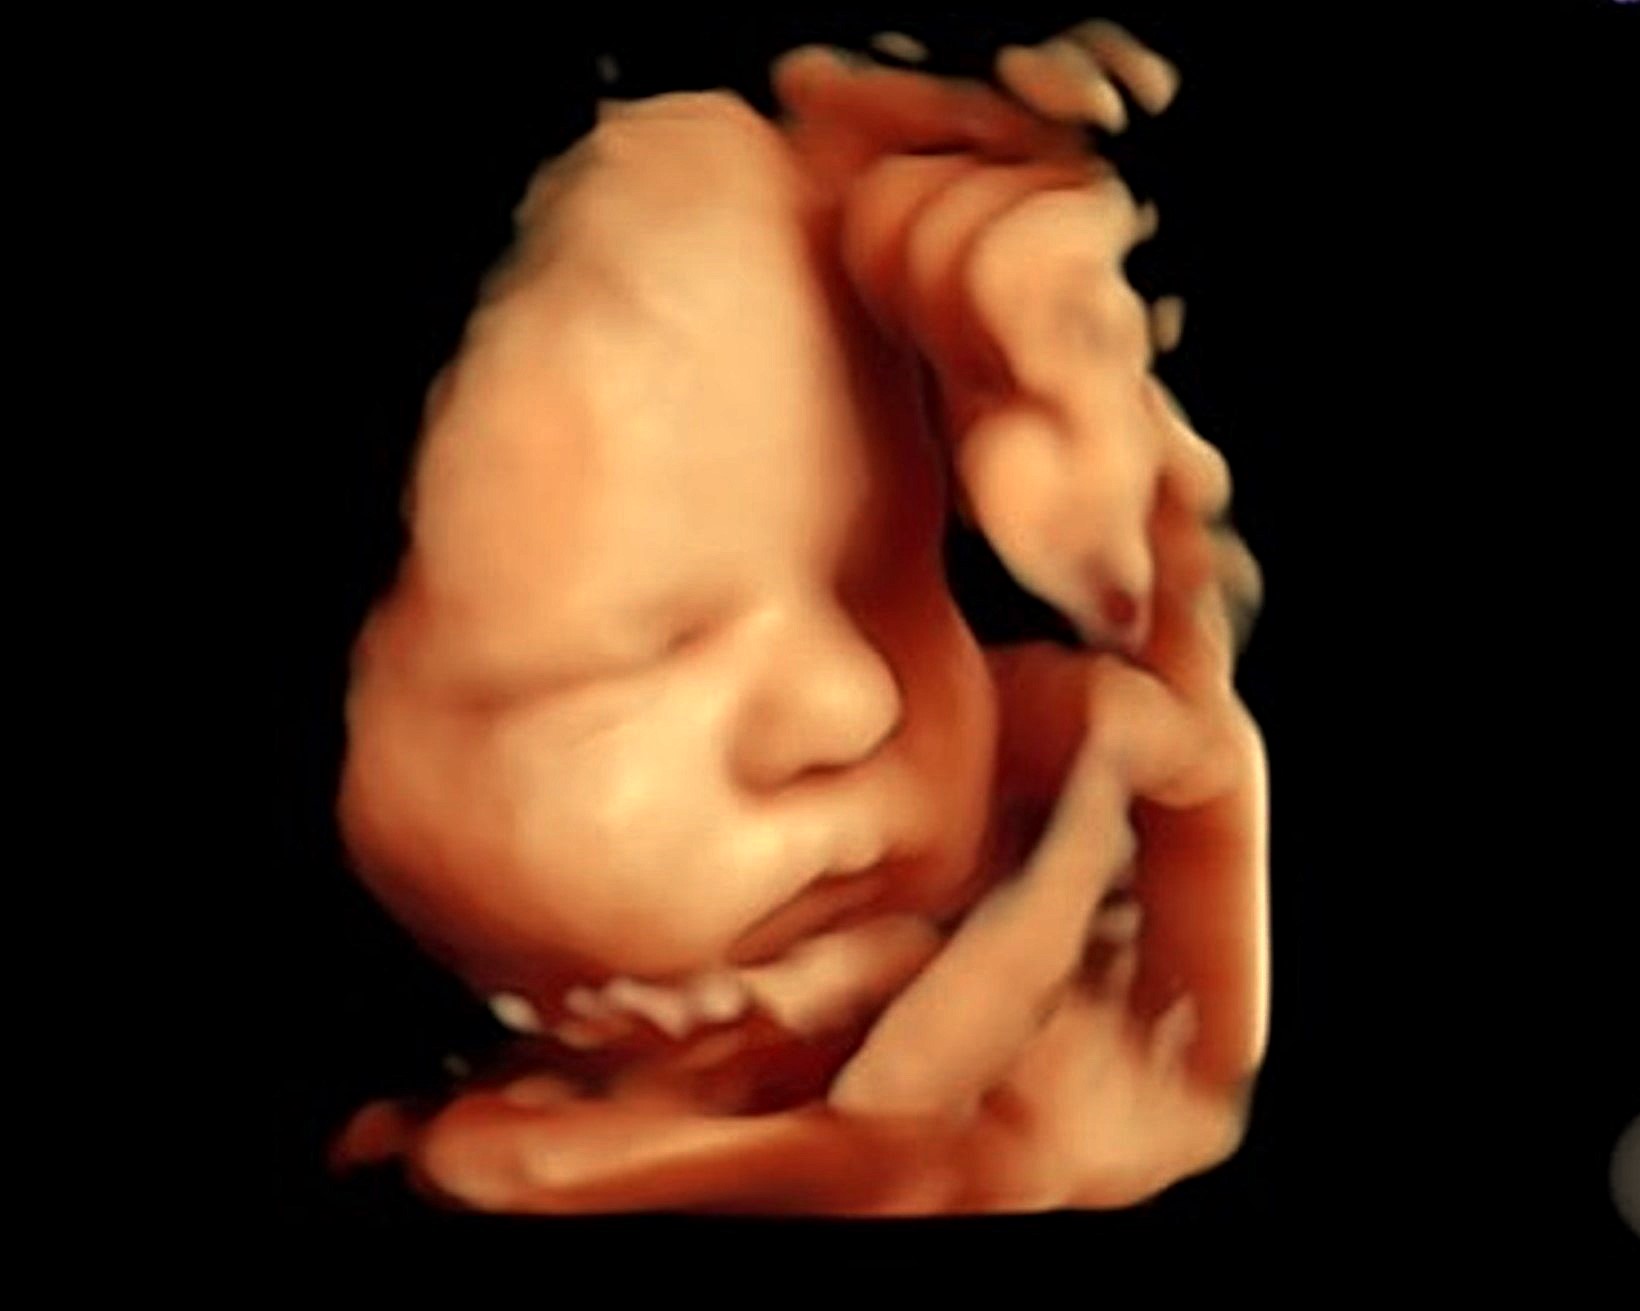

The Growth and Doppler scan will assess how your baby is growing and developing in the later stages of pregnancy.

Using Doppler ultrasound, we also evaluate blood flow in the umbilical cord and baby’s brain, providing important information about placental function and overall fetal well-being.